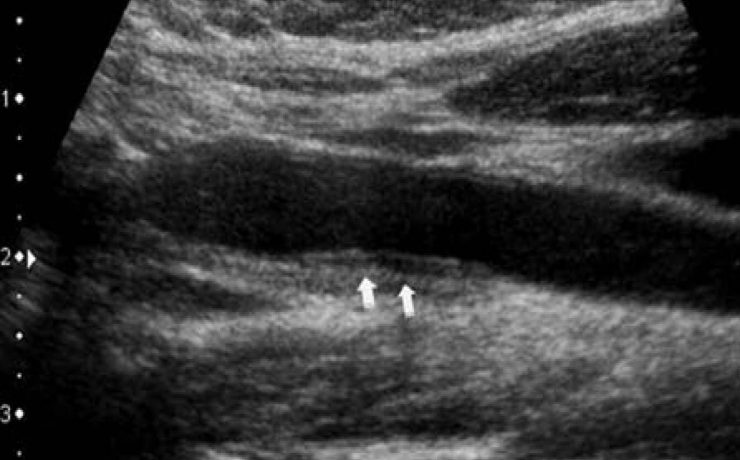

El presente artículo tuvo el objetivo principal analizar la funcion sexual en mujeres portadoras de miomas durante un año, tomando en cuenta el no deseo sexual, la falta de excitación, la falta de orgasmo, presencia de dispareunia y dolor pélvico. El mioma es el tumor solido más frecuente en la